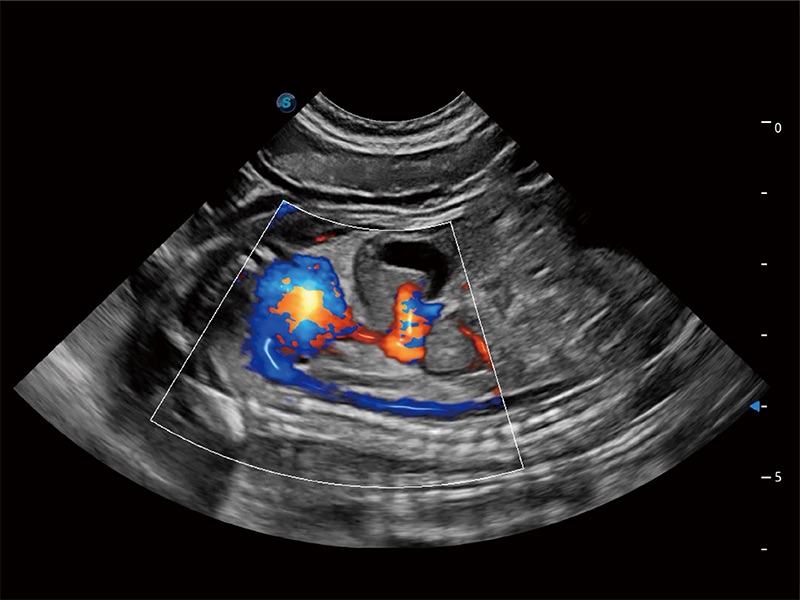

ProPet 80 配備了豐富的心臟探頭群、先進(jìn)的成像技術(shù)和專業(yè)的心臟測量工具,可幫助動物醫(yī)生為不同體型和生理結(jié)構(gòu)的動物提供心臟和心肌功能的全面評估。

實時用顏色表示心肌組織運(yùn)動,觀察和定量組織的運(yùn)動情況,對快速檢測與評估心肌的灌注和活性、電傳導(dǎo)及心肌收縮和舒張功能等均能提供重要的診斷信息。